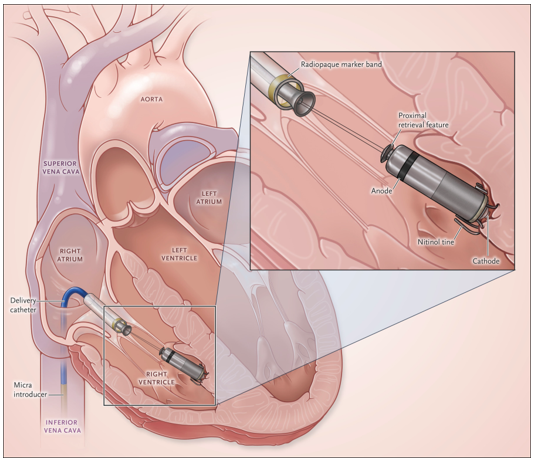

▼ リードレスペースメーカ植え込みの概略図

A Leadless Intracardiac Transcatheter Pacing System.

N Engl J Med. 2016;374(6):533-41. より引用

さらに、2024年度からは当院もリードレスペースメーカ植え込みの施設認定を受けました。従来のペースメーカ植え込みと比較して、手術時間が短縮され、創部も鼠径部の小さな傷のみとなるため感染症のリスクが低減されます。全ての方が適応となるわけではありませんが、適応となる症例に対しては、積極的に植え込みを行っていく予定です。